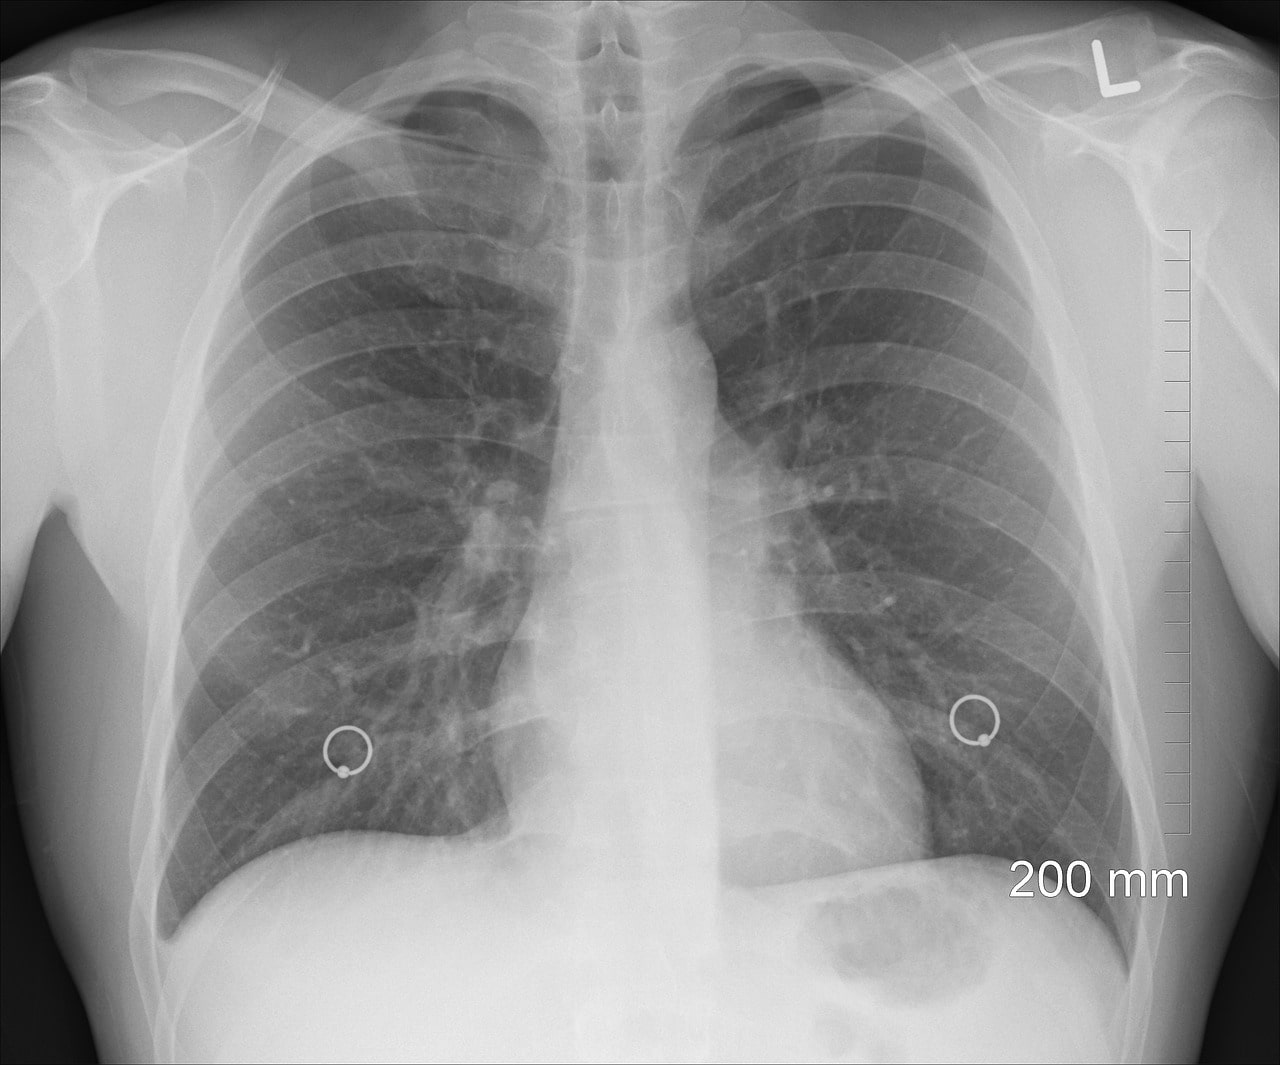

Akciğer sönmesi neden olur? Bilimsel adı pnömotoraks olarak adlandırılan akciğer sönmesi; akciğerin dışındaki plevral boşluğa hava girmesi olayıdır. Plevral boşluğa havanın girmesi, akciğerlerin genişlemesini önler ve büzüşmesine sebep olur. Bundan ötürü kişi nefes darlığı ve ani göğüs ağrısı gibi şikayetler yaşar. Bu hastalıkta, farklı nedenlerden dolayı göğüs boşluğuna hava dolar ve dolan hava, akciğerde baskı yaparak genişlemesine engel olur.

Pnömotoraksta, hava göğüs kafesinde akciğerler arasındaki boşluğu doldurur ve akciğerlere baskı yapar. Böylece akciğer havasını kaybeder ve genişleyemez, büzüşür. Bu hastalık meydana geldiği alan ve etkiye göre, kimi zaman ciddi sonuçlara yol açabilmektedir. Bu sebeple erken tanı ve teşhis çok önemlidir. Akciğer sönmesi neden olur sorusunun cevabı akciğer sönmesi tipine göre değişir. Akciğer sönmesi iki farklı biçimde oluşur:

| Pnömotoraks | Pnömotoraks tipi akciğer sönmesi, halk arasında doğrudan ‘’akciğer sönmesi’’ olarak bilinen tiptir. Çoğu zaman yaşanan akciğer sönmesi bu tipi ifade eder. Pnömotoraksta, akciğerin çevresinde meydana gelen bir baloncuğun patlaması sonucu akciğer ile kaburgalar (göğüs duvarı) arasında hava birikir. Bu durumda akciğer, dıştan gelen basınçtan kaynaklı olarak sönme yaşar ve içine hava dolmaz. |

| Atelektazi | Atelektazi tipi akciğer sönmesi ise soluk borusunda balgam birikmesi veya soluk almayı güçleştiren tümör gibi sebeplerden ötürü gerçekleşir. Bu durumlardan dolayı akciğere yeteri miktarda hava giremeyebilir. Atelektazi tipi akciğer sönmesinde, belirli bir bölgeye hava girişi olmamasından dolayı akciğerde sönme olur. |